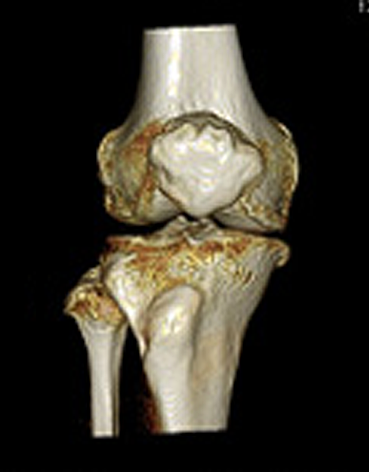

さらにワークステーションを用いる事で、邪魔な骨や臓器を取り除き、任意の方向からの観察が可能となり、レントゲン写真では解りにくい骨折や腹部血管の走行が手術前に確認出来ることで、より正確な診断とより安全な手術が行えます。

<膝関節3DCT>